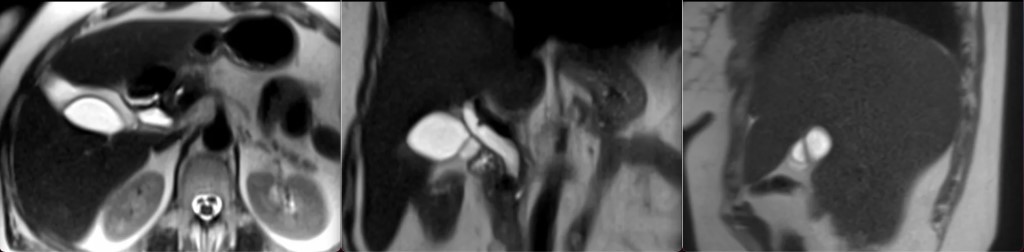

Фото Просто хочу напомнить, что аномалии жёлчного пузыря хоть и крайне редко, но встречаются: держите очередную - перегородчатый жёлчный пузырь. Бывает одна, бывает две, бывает несколько перегородок. Бывает продольная, бывает поперечная, бывает кривая, как здесь. Обычно не имеет клинического значения, некоторые утверждают, что там камни и воспаление легче возникают, но здесь ничего нет. Кстати, на Т1 даже видно, что во всех просветах пузыря есть нормальное изменение структуры жёлчи спереди назад, по типу градиента интенсивности. Что говорит о сохранённой нормальной функции пузыря.